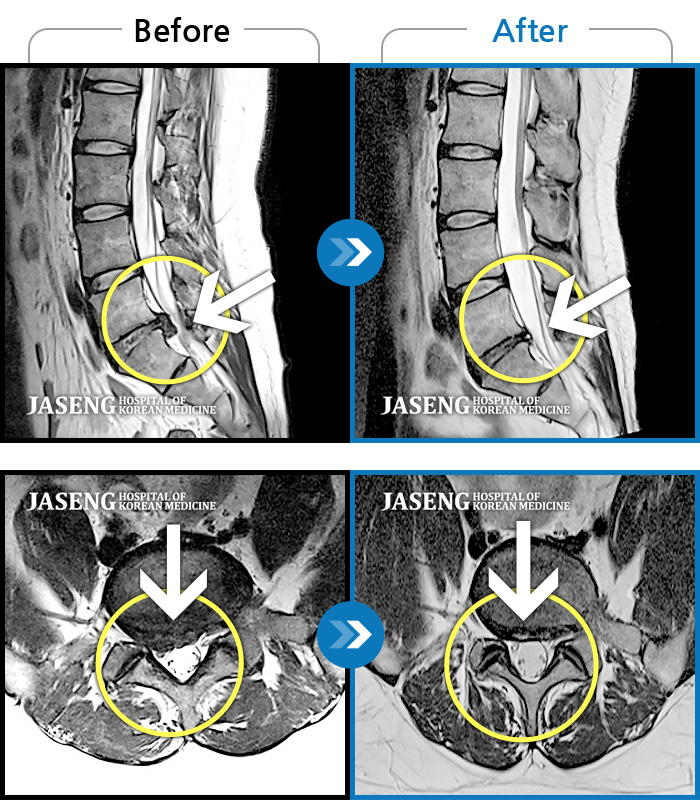

Before

After

환자에게 사전 동의를 받아 동일 조건에서 촬영되었습니다.

개인에 따라 치료 후 부작용이 발생할 수 있으니 의료진과 상담 후 치료를 진행하시기 바랍니다.

허리 뻐근한 통증과 왼쪽 종아리 저림

오른쪽 종아리 당김